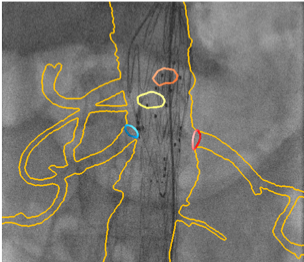

Procédures complexes de réparation endovasculaire des anévrismes abdominaux (EVAR)

Guider